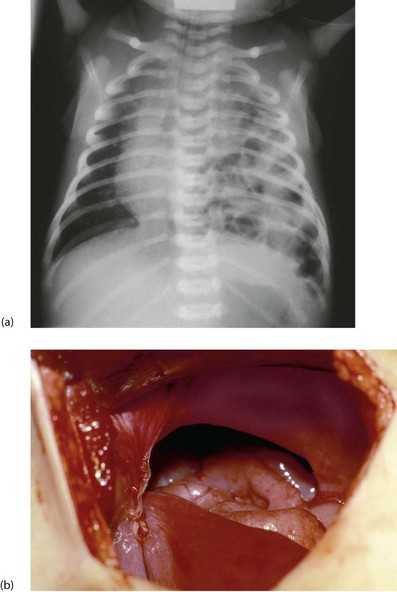

Failure of the pleuroperitoneal canal to close results in the most common type of diaphragmatic hernia (Fig. 50.8b) which is postero-lateral. The incidence is 1 : 3500 live births and 80% are on the left side. Abdominal viscera lie in the chest, displacing the mediastinum. Lung development is abnormal, with fewer branching events during development causing variable pulmonary hypoplasia (Fig. 50.8a), which may be so severe as to be incompatible with life.

Fig. 50.8 Congenital diaphragmatic hernia

(a) Plain chest X-ray showing air-containing loops of bowel in the left chest and displacement of the mediastinum to the right. Note the endotracheal tube in place to allow assisted ventilation. (b) An operative picture viewed from the abdomen, showing the pleuro-peritoneal canal defect in the diaphragm. Some of the intestine had already been reduced from the thorax

Diagnosis is now frequently made at antenatal screening. Soon after birth, the infant develops respiratory distress; survival depends on adequate residual lung volume and function. Cyanosis, mediastinal shift and an ‘empty’ (scaphoid) abdomen are the classic signs and the diagnosis is confirmed on chest X-ray following passage of an orogastric tube. Cardiac malformations are commonly associated.